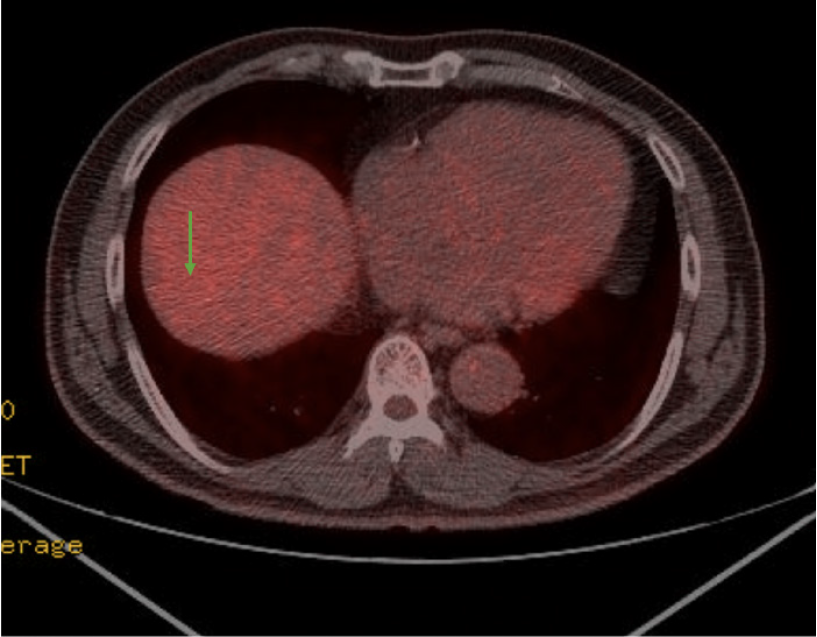

Torso PET-CT findings were more suggestive of a benign mass than a malignancy, with no metabolic evidence of local recurrence or regional lymph node involvement (Figure 2).

Based on imaging findings, a 3 cm liver mass was identified in segment 8 (Figures 1 and 2), with no evidence of distant metastasis to the abdomen or chest. Based on these findings, a radical resection was performed. Considering the advantages of minimally invasive surgery, a laparoscopic right anterior sectionectomy was performed.